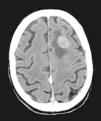

Casi 3 meses después del alta hospitalaria, el paciente ingresó por cuadro confusional agudo severo, secundario a una crisis convulsiva tónico-clónica. Se solicitó la realización de TAC craneal (fig. 13), que confirmó la sospecha clínica de metástasis cerebral.